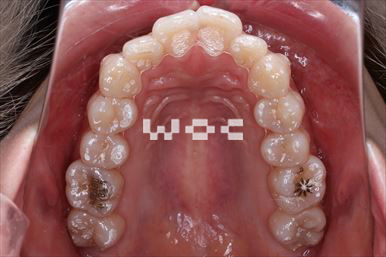

出っ歯エッジワイズ装置

特に装置の希望はなかったので、エッジワイズ装置を選択。

歯の移動量が大きいので歯根吸収の可能性がありましたが、目立った吸収は見られませんでした。-

治療中1

- 年齢:17歳女性

- 主訴:出っ歯、前歯のガタガタが気になる

- 基本矯正料金:78万円

- 治療期間:1年2ヶ月

- 抜歯部位:上顎両側第一小臼歯